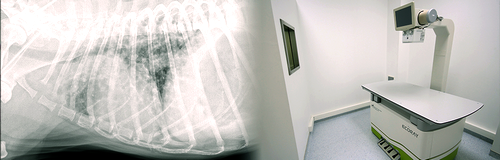

Radyoloji ünitesinde bu amaca hizmet edecek sadece küçük hayvanlar için özel olarak tasarlanmış ve görüntüleri dijital ortama aktaran bir dijital radyografi (DR) cihazı vardır. Bu cihaz sayesinde hastanın görüntüleri saniyeler içinde, arada herhangi başka bir işleme gereksinim göstermeksizin ekranda görülebilir hale geliyor. Daha sonra oluşturulan bu görüntüler değerlendirilirken, istendiği kadar büyütülüp, parlaklık ve kontrast ayarları değiştirilerek incelenebilir. Bu özellikler konvansiyonel radyografiye göre çok büyük üstünlükler sağlamaktadır. Bu cihazla Chihuahua’dan St. Bernhard ırkı köpeğe kadar, muhabbet kuşundan Ara papağana kadar her cüssede hasta muayene edilebilir. Görüntüler alındıktan sonra kaydedilebiliyor, e-posta ile gönderilebiliyor, bozulmadan arşivlenebiliyor ve bu sayede hem kontrol muayeneleri için faydalı olmakta, hem de eğitim-öğretim ve bilimsel çalışmalarda mükemmel bir materyal kaynağı oluşturmaktadır.